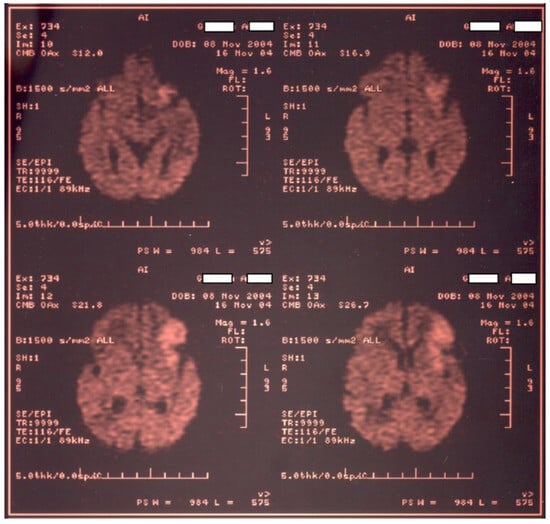

Newborn #1 (3000 g/50 cm, female) was born at 36–37 weeks of gestation by caesarean section after an uneventful pregnancy and was the first child of a healthy mother. The Apgar score was 9, the transition to the extrauterine environment was smooth, and the clinical examination after birth was normal. At 36 h of life, the baby developed tonic–clonic seizures of the left hemibody associated with cyanosis, apnea, and bradycardia and was admitted to the NICU. The baby was tested for metabolic causes of the seizures; a lumbar puncture and inflammatory panel and bacteriologic tests were performed, and phenobarbital was started. Because of recurrent apneic spells, respiratory support was initiated, and imagistic investigations were ordered. Head ultrasonography raised suspicion of a large right frontal–parietal infarction, confirmed later through Computer Tomography (CT) and Magnetic Resonance Imaging (MRI)—see Figure 1 and Figure 2. Echocardiography revealed no abnormalities. Laboratory tests were all within normal limits, except a mild thrombocytopenia (105,000/mmc).

Figure 2. MRI examination for newborn #1 confirms a large right frontal–parietal infarction.